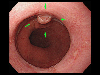

A case of IIc+IIa type early gastric cancer which invaded the esophagus.

Endoscopy